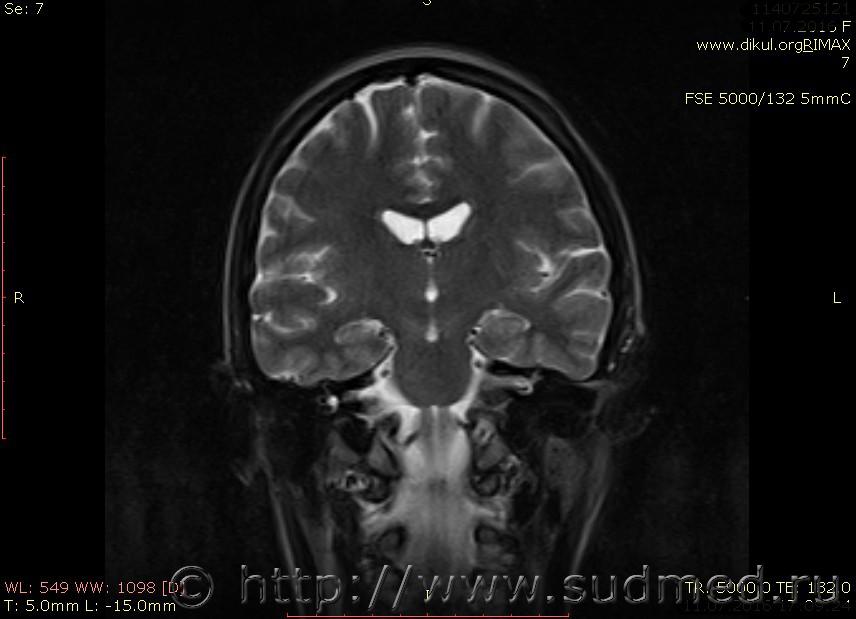

МРТ головного мозга показало: МР-данных за наличие очаговых изменений в веществе головного мозга на момент исследования не выявлено. МР-признаки нарушения соотношения в атланто-осевом суставе. Определяется ассиметрия положения зубовидного отростка С2 относительно боковых масс С1(справа 6,5; слева 4 мм.)

Сама по себе эта информация даёт основания подозревать вывих первого шейного позвонка, но однозначно не свидетельствует о наличии вывиха. Нужно смотреть на снимках наличие реакции со стороны мягких тканей, в т.ч. связочного аппарата, нужно анализировать особенности неврологической патологии, её динамику и проч.

Запрошен электронный вариант снимков из учреждения, где делалось МРТ. Т.к. с самого снимка делать копии не получается,очень мелкие кадры. Завтра попробую вставить в сообщение. (Но СМЭ снимок не смотрел, смотрел только мед.карту, в которой находилось описание МРТ).

Посмотрите пожалуйста снимки, надеюсь на них видны позвонки С1,С2?

Прошу прощения, попробую снова прикрепить файлы. Данные учреждения и пациента убраны.